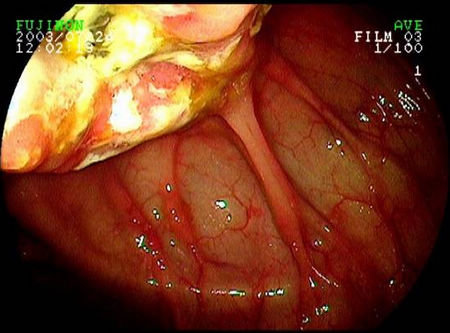

梅克尔憩室

梅克尔憩室(Meckels diverticulum)是在胚胎发育过程中卵黄管退化不全所形成的回肠远端憩室。临床上多无症状往往因憩室出现并发症表现才就诊而获诊断。

Meckel憩室是真性憩室,发生率为2 ~ 3%,位于小肠的对系膜侧,一般位于距回盲瓣100 cm以内,约半数具有异位胃粘膜,可发生溃疡、出血。